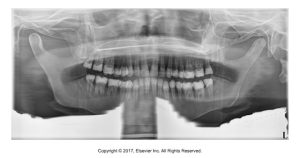

A dark radiolucent band covers the apices of the maxillary teeth on the pano, making them hard to evaluate.

Tongue was not placed against the palate